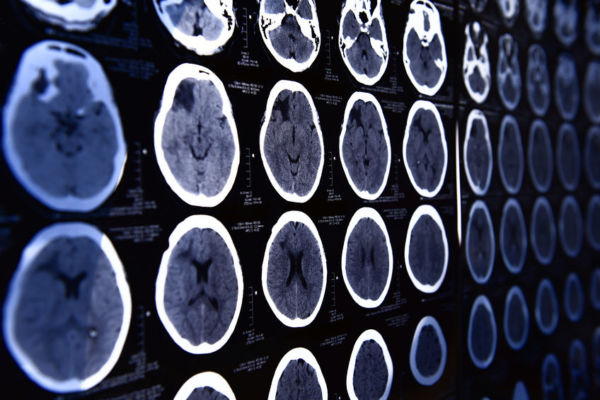

The Australian Sports Brain Bank opened earlier this year and is looking into the impact of repetitive concussions on the brain.

The condition is known as chronic traumatic encephalopathy (CTE), and it can’t be diagnosed until after a person has died.